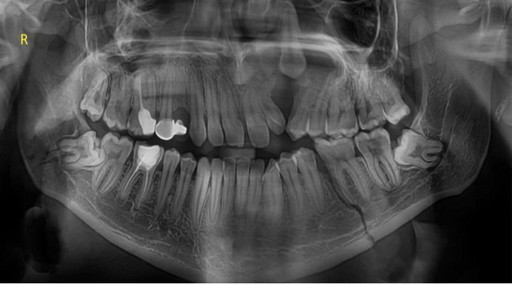

Лінії розлому, зміщення, фрагментацію; етапи зрощення та нормальної консолідації

Ознаки переломів і оцінка консолідації